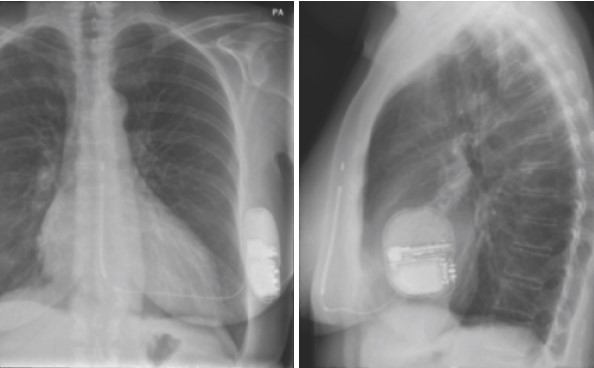

I defibrillatori tradizionali, utilizzati per il trattamento delle aritmie ventricolari e per combattere la morte improvvisa, necessitano dell’inserzione di cateteri endovascolari che vengono cioè fatti passare attraverso i vasi che arrivano al cuore. I nuovi defibrillatori sottocutanei, al contrario, non prevedono tali cateteri, ma vengono impiantati appunto a livello sottocutaneo (Fig. 1).

Fig. 1

Un singolo catetere viene fatto passare sotto la pelle, dal defibrillatore situato in una tasca sotto l’ascella verso la porzione anteriore del torace lungo il margine dello sterno.